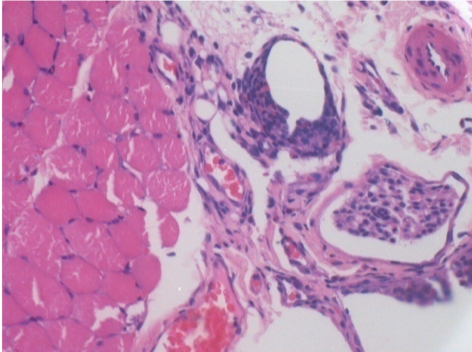

1 mes después de la inyección de Endopeel 0,1 ml en el músculo pretibial derecho.

¡Lo que se ve en negro en las imágenes no es una necrosis como podrían imaginar algunos científicos!

De hecho, hay que tener en cuenta 4 conclusiones

08